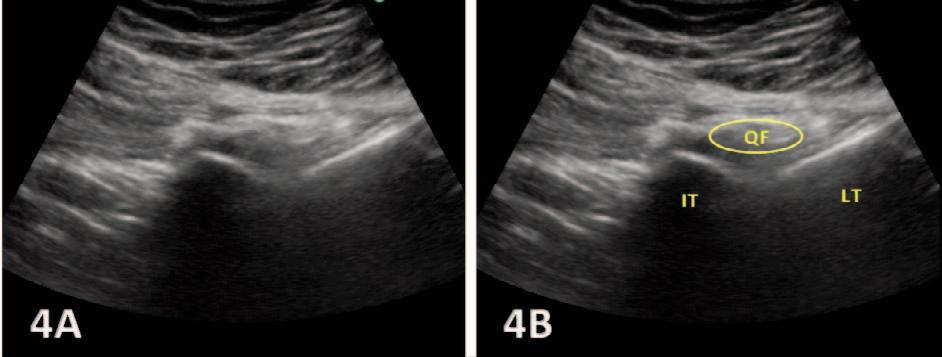

MSK ULTRASOUND BITES: Tips and Tricks

The Utilization of Diagnostic Musculoskeletal Ultrasound in the Evaluation for Ischiofemoral Impingement: A Perspective for Rehabilitation Providers. Manske RC, Wolfe C, Page P, Voight M, Bardowski B.